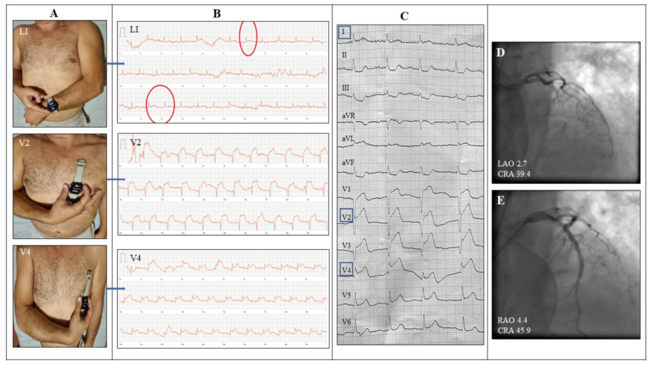

Τo increase diagnostic potential, he was instructed to place the smartwatch onto the 4th intercostal space (ICS) left of the sternum touching the crown with his right index finger and then repeat on the 5th ICS along the midclavicular line (Figure 1A). By this manipulation, precordial leads V2 and V4 were reproduced successively and an anterior ST-elevation myocardial infarction was depicted (Figure 1B). The patient bypassed the emergency department (ED) triage and headed directly to the cath lab. In-hospital electrocardiogram leads I, V2, and V4 demonstrated notable correlation with patient’s self-recordings (Figures 1B and 1C). Coronary angiography revealed a left anterior descending artery occlusion, which was successfully stented (Figures 1D and 1E).

Smartwatches have been FDA-cleared for rhythm detection but ST-T deviation recognition is also feasible. These gadgets record the voltage difference between the positive sensor embedded in the back and the negative sensor integrated in the crown, thus reproducing bipolar leads similar to Einthoven’s I, II, III, or Wilson’s precordial V1-V6 with suitable placing manipulation (Figure 1A).